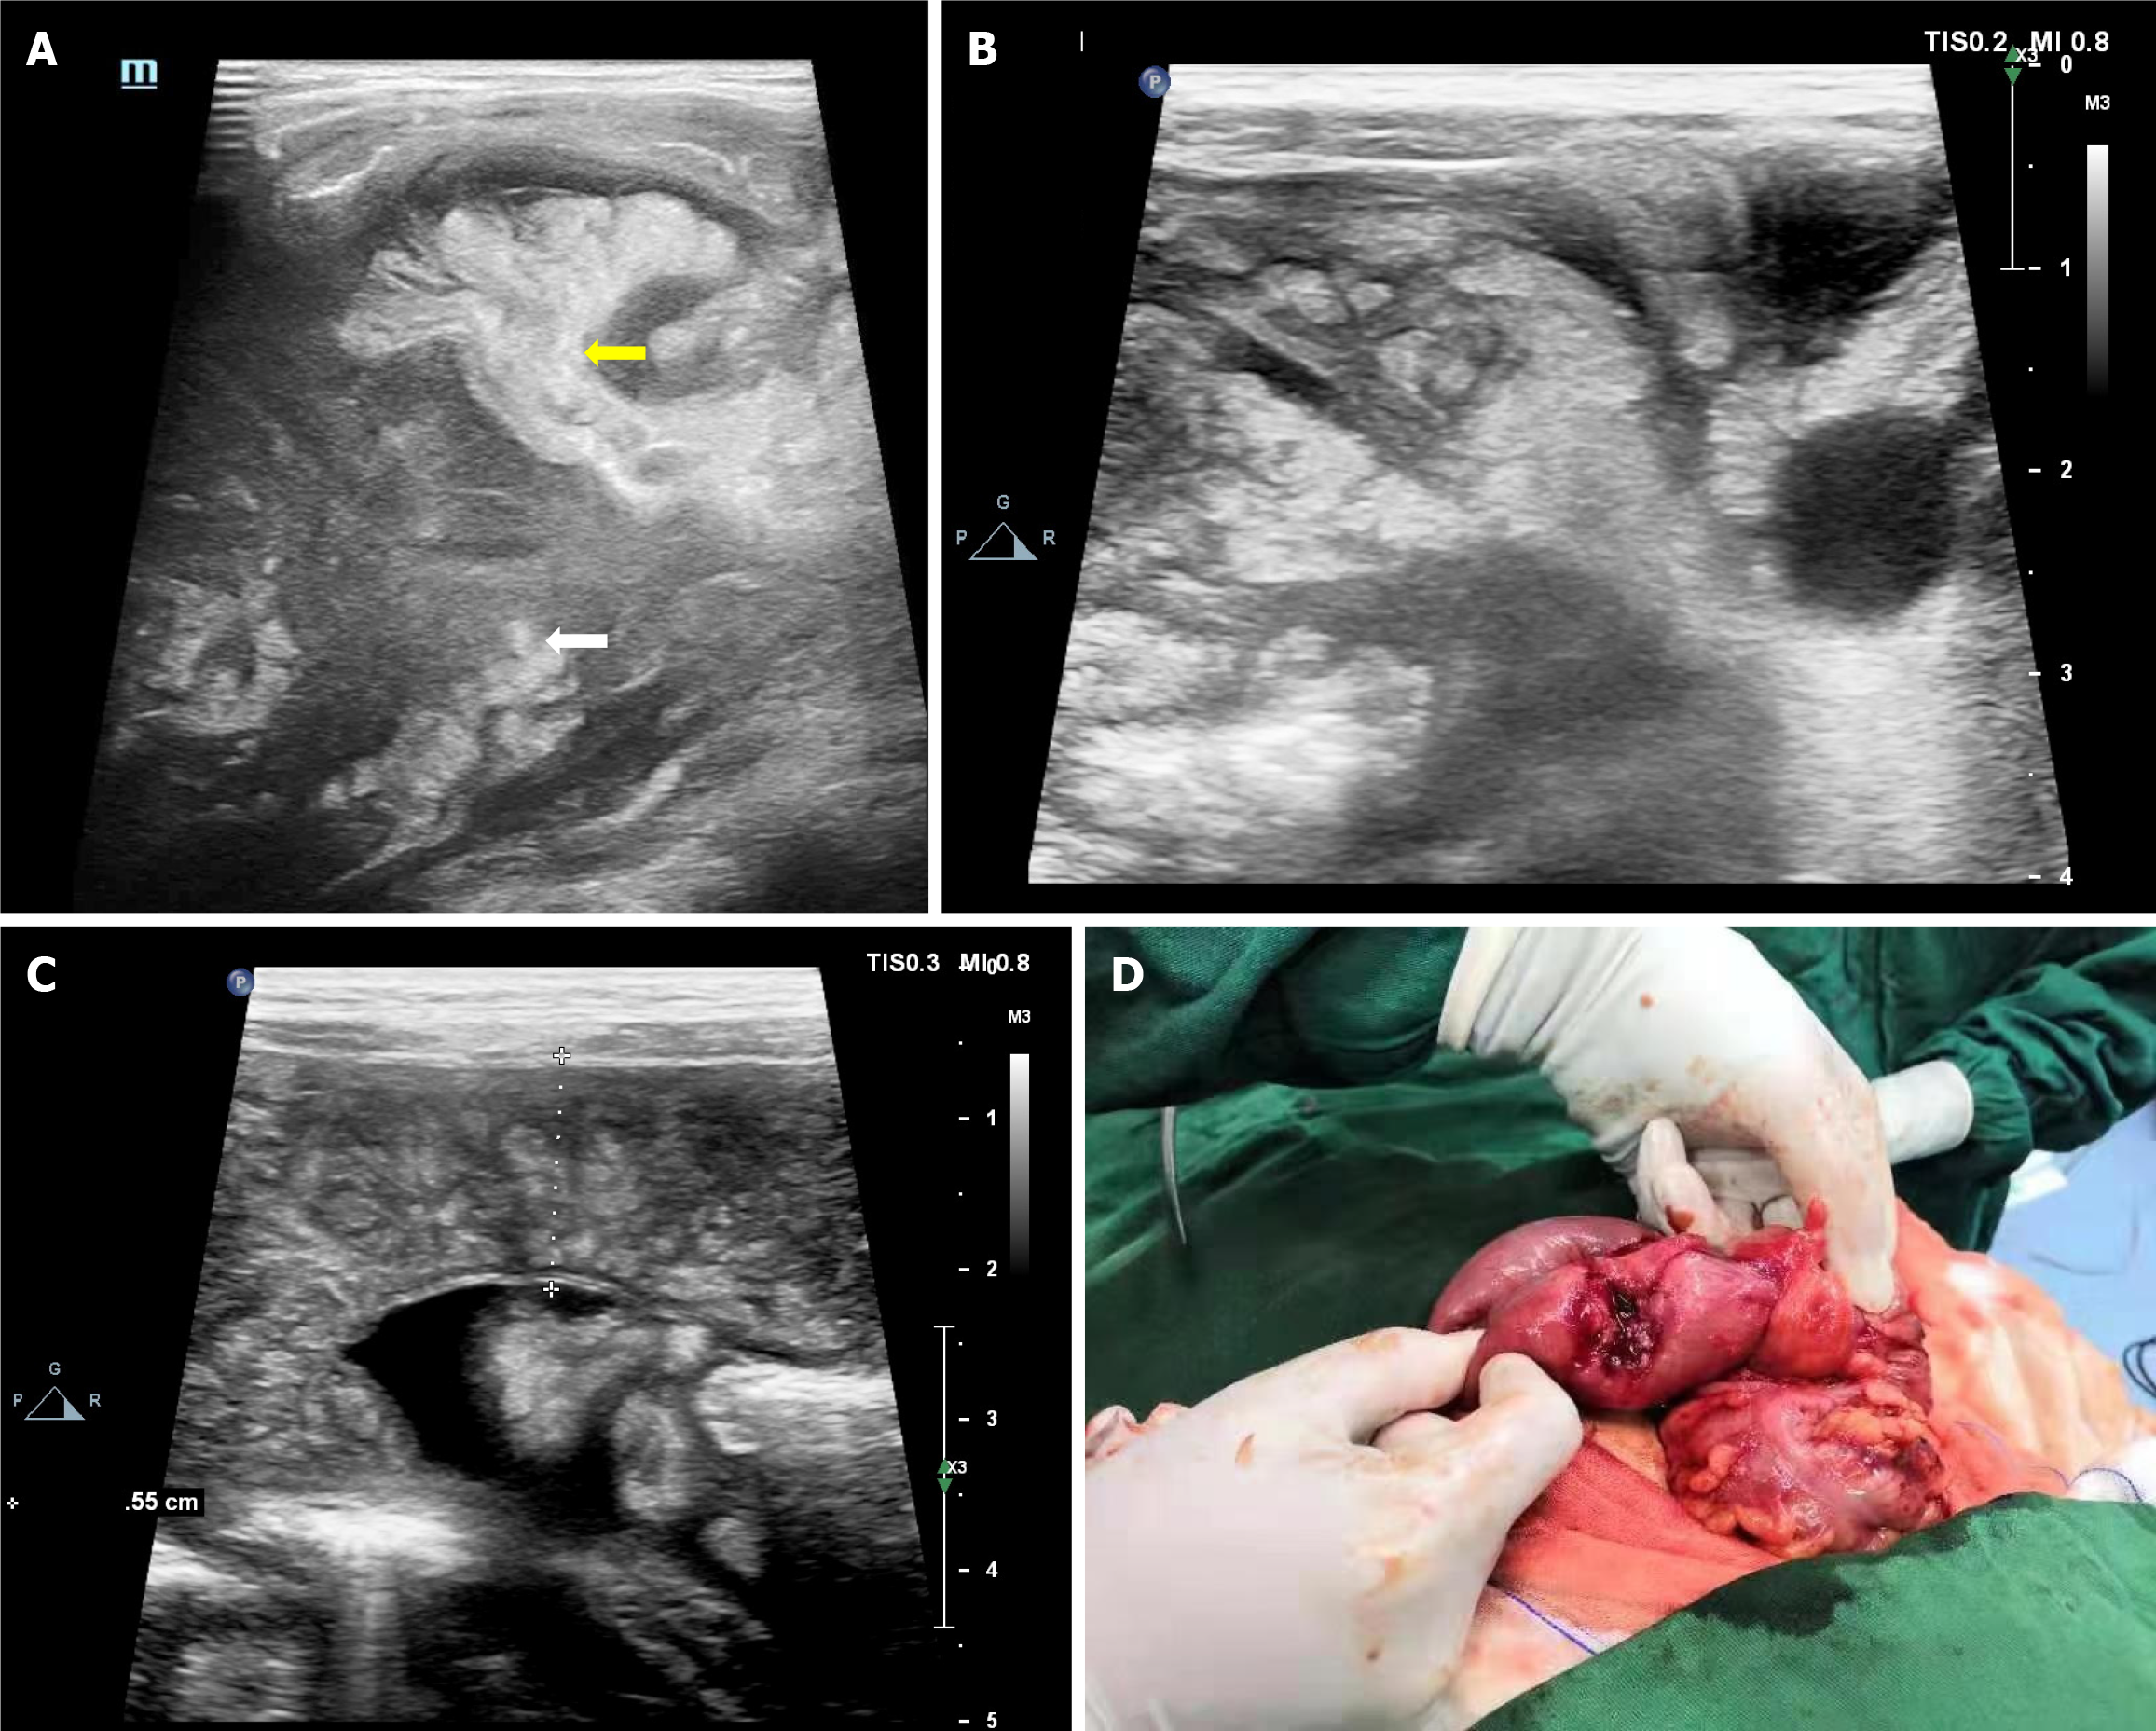

Figure 3 Manifestations of abdominal cavity and organ invasion in intestinal lymphoma.

A: The intestinal wall (sigmoid colon and rectum) of the primary part was circular thickening thickened, with decreased echo and small intestinal lumen; B: In the remaining abdominal cavities, the intestinal wall was widely thickened, and the thickening was not as obvious as that of the primary lesion, with interintestinal effusion; C and D: Extremely hypoechoic distributed along the Greenland sheath in the liver and multiple hypoechoic metastatic foci in the liver; E: A widely distributed low-echo area was observed around the pancreas; F: Scattered low-echo areas in the kidney.